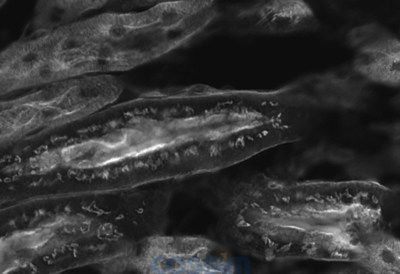

小鼠腎臟熒光圖像(單色)的比較 使用傳統(tǒng)模型“DS-Ri2”獲取圖像

小鼠腎臟熒光圖像(單色)的比較 使用常規(guī)模式“Digital Sight 10”獲取圖像